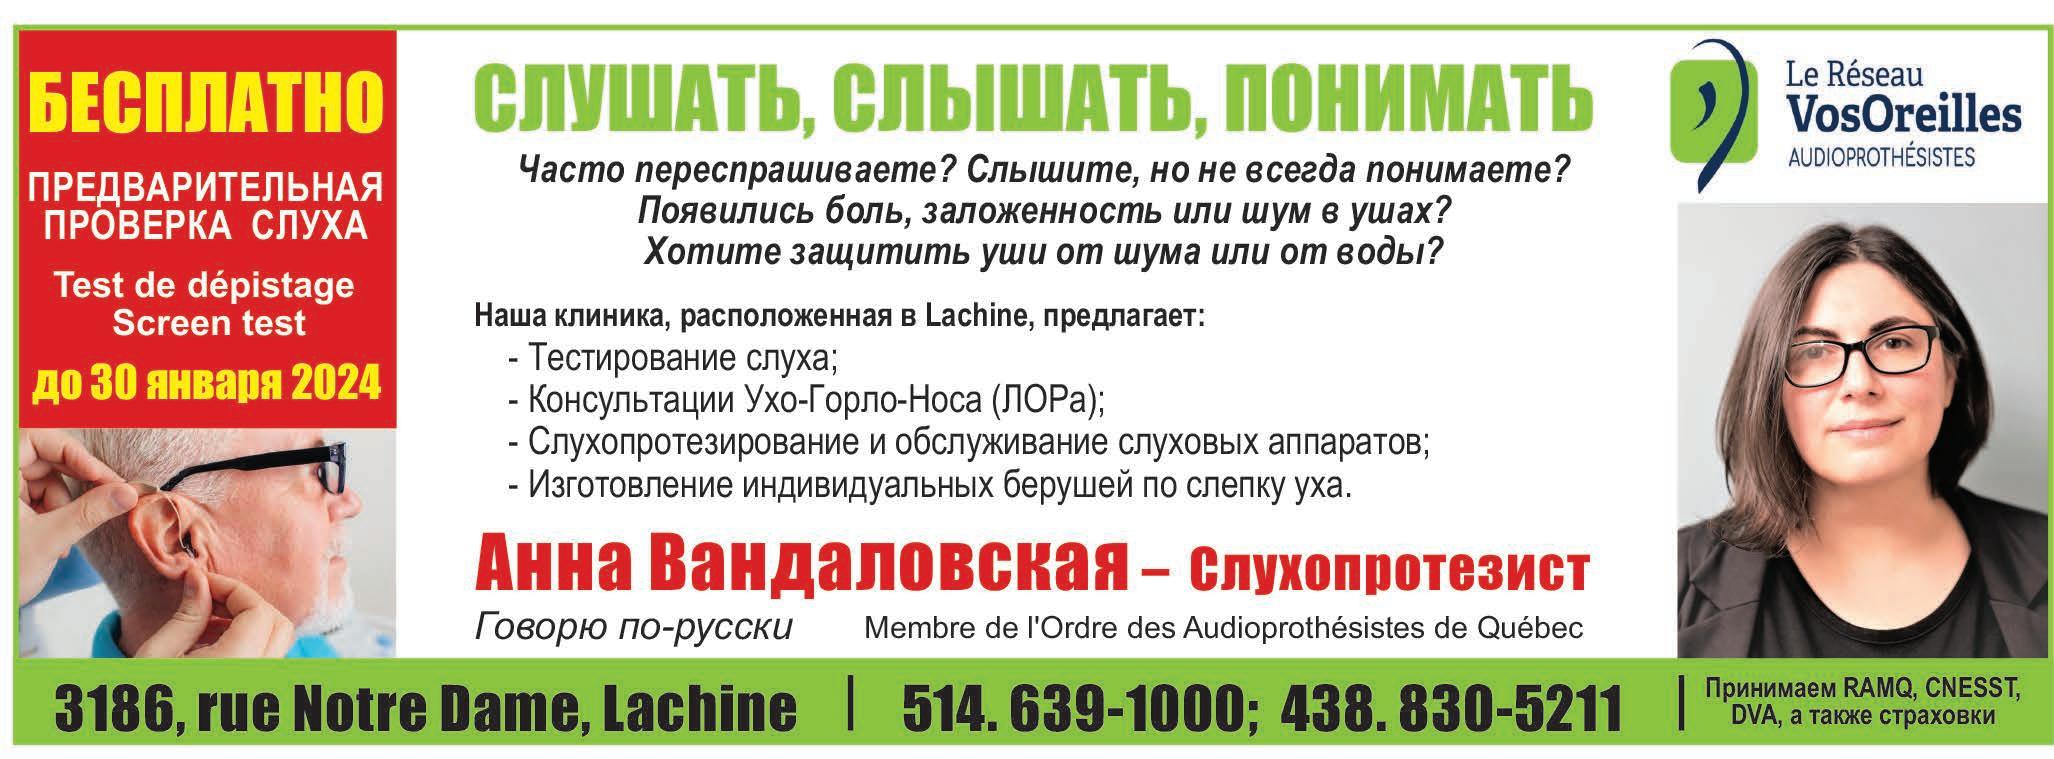

несомненно,являетсяпресбиакузис-возрастное снижениеслуха.Имстрадаютболеетретилюдейввозрастеот60до70летипочти80%людейстарше80лет. Вначалевозрастнаяпотеряслухапроявляетсяввидеухудшенияслышимостивысокихчастот.Высокие звукивчеловеческойречичащевсегосоответствуют согласным,анизкие—гласным.Рольгласныхсостоит втом,чтобыпридатьречиоболочку(огласку),асогласных—ясностьичеткость.Привозрастномизменениислухаучеловекагласныесохраняются,а согласныесловнотеряются.

Увы,пресбиакузисковарен.Человекукажется,что онслышит,ноплохопонимает.Ондумает,чтоокружающиеговорятдостаточногромко,ноневнятнопроизносятслова,словнопроглатываютнекоторыезвуки. Унегосоздаетсявпечатление,чтовсевокругразучилисьнормальноговорить.Человекстановитсяраздражителенинетерпимксобеседникам.Ксожалению,возникающеенепониманиезачастуюсписываетсянавозрастисвязанноеснимухудшениевосприятияикогнитивныхспособностей.Из-за отсутствияпониманияитрудностейвобщении,люди

сподобнымипроблемамисклонныксамоизоляции. Имбольшеневрадостьвстречисблизкими,визиты детейивнуков.Человекстараетсяизбегатьшумныхи людныхмест.Емустыдночувствоватьсебяпотерянным,киватьневпопад,кпримеру,вресторанеи не смочьподдержатьинтереснуюбеседу.Происходитэтокакразвтомвозрасте,когдачеловекостронуждаетсявприсутствииблизких.Сглухотойпостепенноотмираетнетолькосоциальная,но икультурнаяжизнь.Пропадаетинтерескфильмами спектаклям:ведьнепонятно,чтопроисходитнасцене. Человекнесмеетсянадшуткаминепотому,чтоне понял,апотому,чтонерасслышал.Музыканеприноситбылогоудовольствия.Измузыкальныхпроизведенийисчезаютцелыепартии,например,скрипок,или кажется,чтомузыкантыфальшивят.

Крометого,из-заухудшенияслухамозгнедополучаетзвуковойстимуляции.Этодо40%увеличивает рискразвитияболезниАльцгеймераиливозрастного слабоумия. Есливычастопереспрашиваете,проситесделать погромче,избегаетевстречвшумныхместах,крайне желательнопровеститестированиеслуха.До30января2024годавнашейклиникеможно пройтиПРЕДВАРИТЕЛЬНУЮПРОВЕРКУСЛУХАTest

dedépistagegratuit(фр.)/freescreentest(англ.)БЕСПЛАТНО.

Вслучаевыявленияглухотывампредоставятуслугиаудиолога,врача-отоларингологаи-принеобходимости-слухопротезиста.

Современныеслуховыеаппаратыпрактическинезаметны,легкивношениииэксплуатации.Единственнымсожалениемостанетсялишьто,чтоне обратилисьзапомощью,кактолькозакралисьподозрения,чтосослухомневсевпорядке.

Исправлениеслухаповыситкачествожизни,вернуввнеещебетптиц,журчаниеводы,детскийлепет, звукимузыки,аглавное–возможностьобщениясокружающими.

(Membre de l’Ordre des Audioprothésistes de Québec)